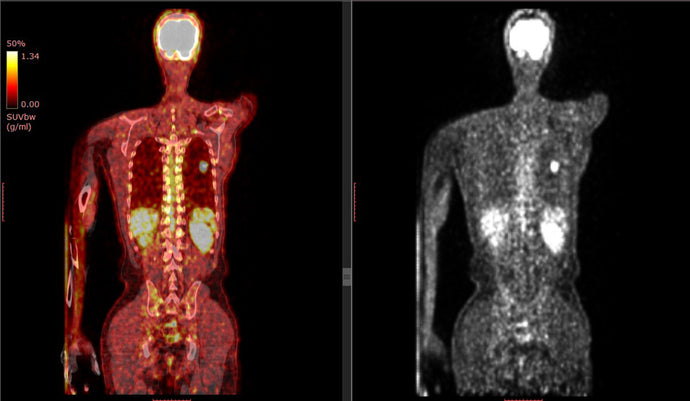

Study of 50,000 people finds brown fat may protect against numerous chronic diseases

Date: January 4, 2021 Source: ScienceDaily Summary: By far the largest of its kind in humans, the study confirms and expands the health benefits o...